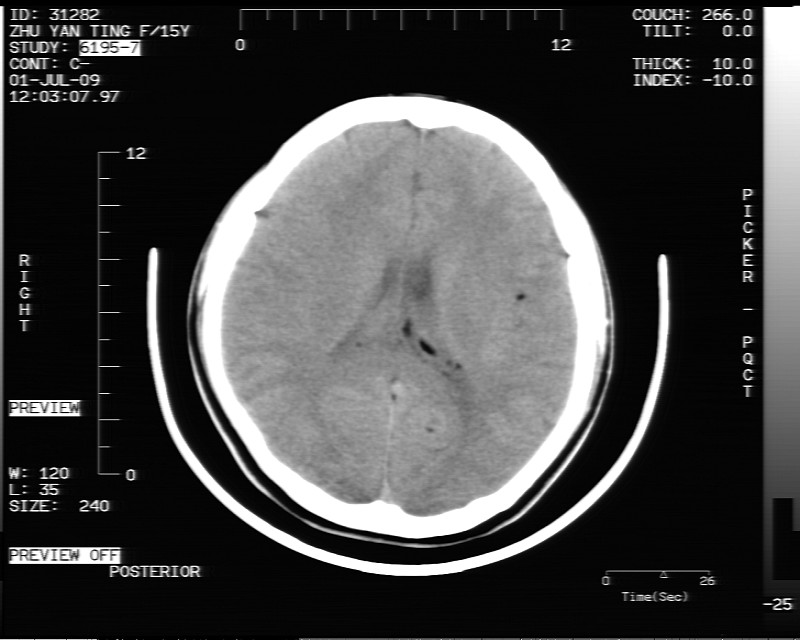

以下是引用余辉在2009-7-1 17:20:00的发言:[br]病变ct值-20至-80[br]考虑脑内脂肪瘤破裂,瘤主体应该在右侧桥小脑角池及鞍上池[br]鞍上池病灶面积较大,ct值应该能够测准,应此病灶应该就是脂肪密度,病灶密度有ct值-20至-80hu,为成熟脂肪密度,因此考虑脂肪瘤,也不除外其他含成熟脂肪的病灶[br]皮样囊肿密度应该稍高一点